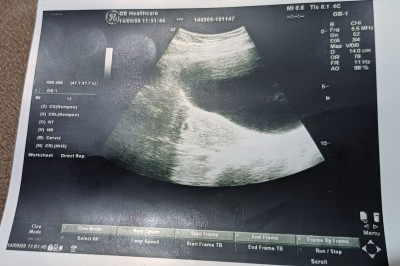

Ultrasonda ao nedir ao%98 D14cm bilen cevaplaya bilirmi

ao bebeğin kalbinden çıkan aort atardamarınin kısaltmasidir D12 de kese çapı umarım doğru bilgilendirmisimdir. Yanlışsa düzeltsinler

Kalp atışı duyulmadı peki normalmi

Yazdım canım ama çıkmadı kese yi gördük ama kalp atisi duymadık tedirginim